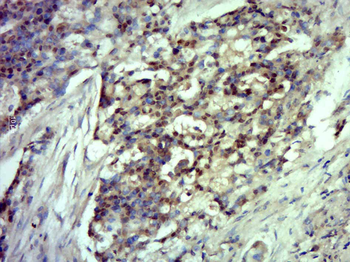

Antibody used in IHC on Human Skin at 4.0-8.0 ug/ml.